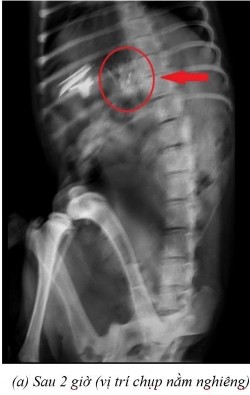

Phụ lục 5.2. Hình ảnh X-quang chó 3 ở thời điểm (a) sau 2 giờ 15 ở vị trí nằm ngửa, (b) sau 4 giờ ở vị trí nằm ngửa, (c) sau 7 giờ ở vị trí nằm ngửa và (d) sau 9 giờ ở vị trí nằm ngửa